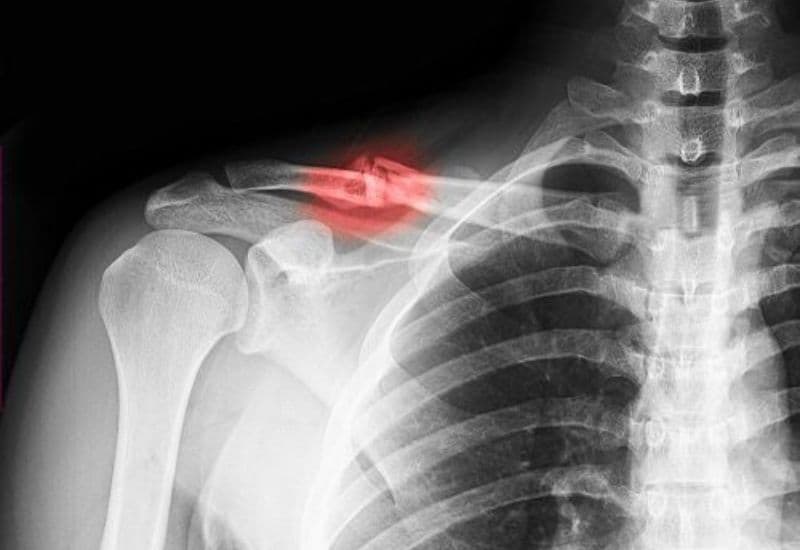

4. Chẩn đoán gãy xương đòn: Cần xác định chính xác mức độ tổn thương

Việc chẩn đoán chính xác là bước đầu tiên và quan trọng nhất trong điều trị gãy xương đòn. Bác sĩ sẽ thăm khám lâm sàng để xác định vị trí đau, biến dạng vai và giới hạn vận động của bệnh nhân. Sau đó, các phương pháp chẩn đoán hình ảnh có giá trị cao sẽ được chỉ định để đánh giá chi tiết tình trạng gãy, mức độ di lệch và xem có tổn thương mô mềm hay mạch máu đi kèm hay không.

Việc xác định rõ vị trí gãy và phân tích đặc điểm mảnh xương gãy là cơ sở để bác sĩ quyết định phương pháp điều trị phù hợp nhất: phẫu thuật hay bảo tồn.